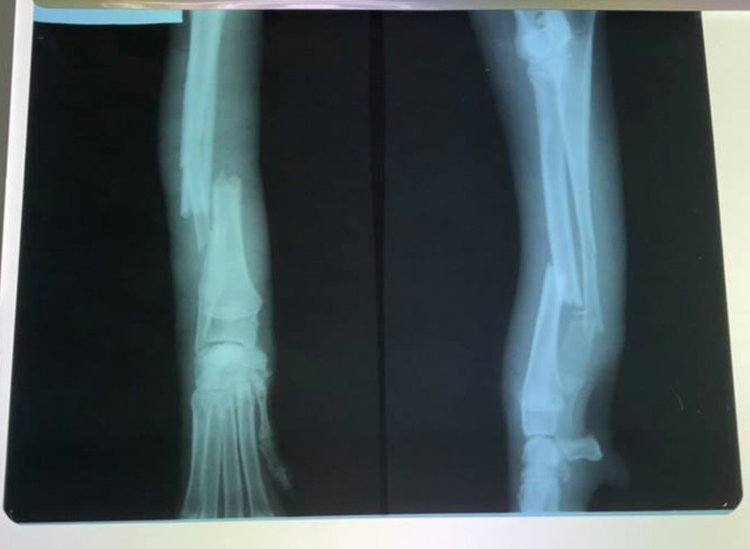

Спешно се стърси стопанин за куче, спасено след катастрофа край Хасково. Преди дни  четириногото е открито със счупен крак край картинг пистата, където е било блъснато от кола. На него се натъкнала хасковлийката Анелия Запрянова, която се прибирала към областния град. Младата жена го откарала в места клиника за лечение като в спасителната акция се включили и други преминаващи хора. Престоят и лечението му ще бъде покрито със средства от дарители.

Кучето предстои да бъде изписано утре, каза Анелия. Тя поясни, че то е женско и тъй като не му знае името на галено го нарича Клепоушка, която ходи и е в добро здравословно състояние. Важно е в първите дни да не се движи много, за да му заздравее крака.